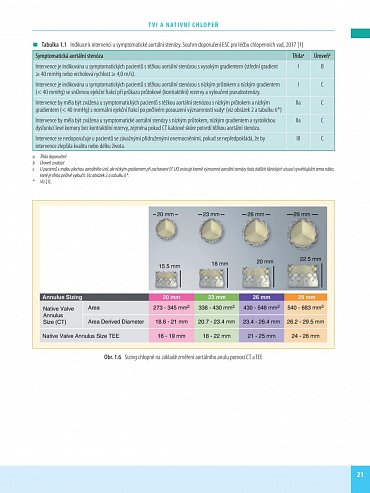

Transkatétrová implantace chlopní (TVI) je minimálně invazivní výkon umožňující náhradu poškozené srdeční chlopně - aortální nebo mitrální. Preferuje se zejména u pacientů s vysokým rizikem komplikací chirurgického výkonu na otevřeném srdci. Kniha obsahuje velký počet pečlivě vybraných kazuistik se stručným schématem diagnostického postupu, diferenciální diagnostikou a technikou operace. Vlastní popis je doplněn množstvím zobrazovacích vyšetření a peroperačních fotografií, které umožní orientaci čtenáře a pochopení základních kroků diagnostiky a léčby.